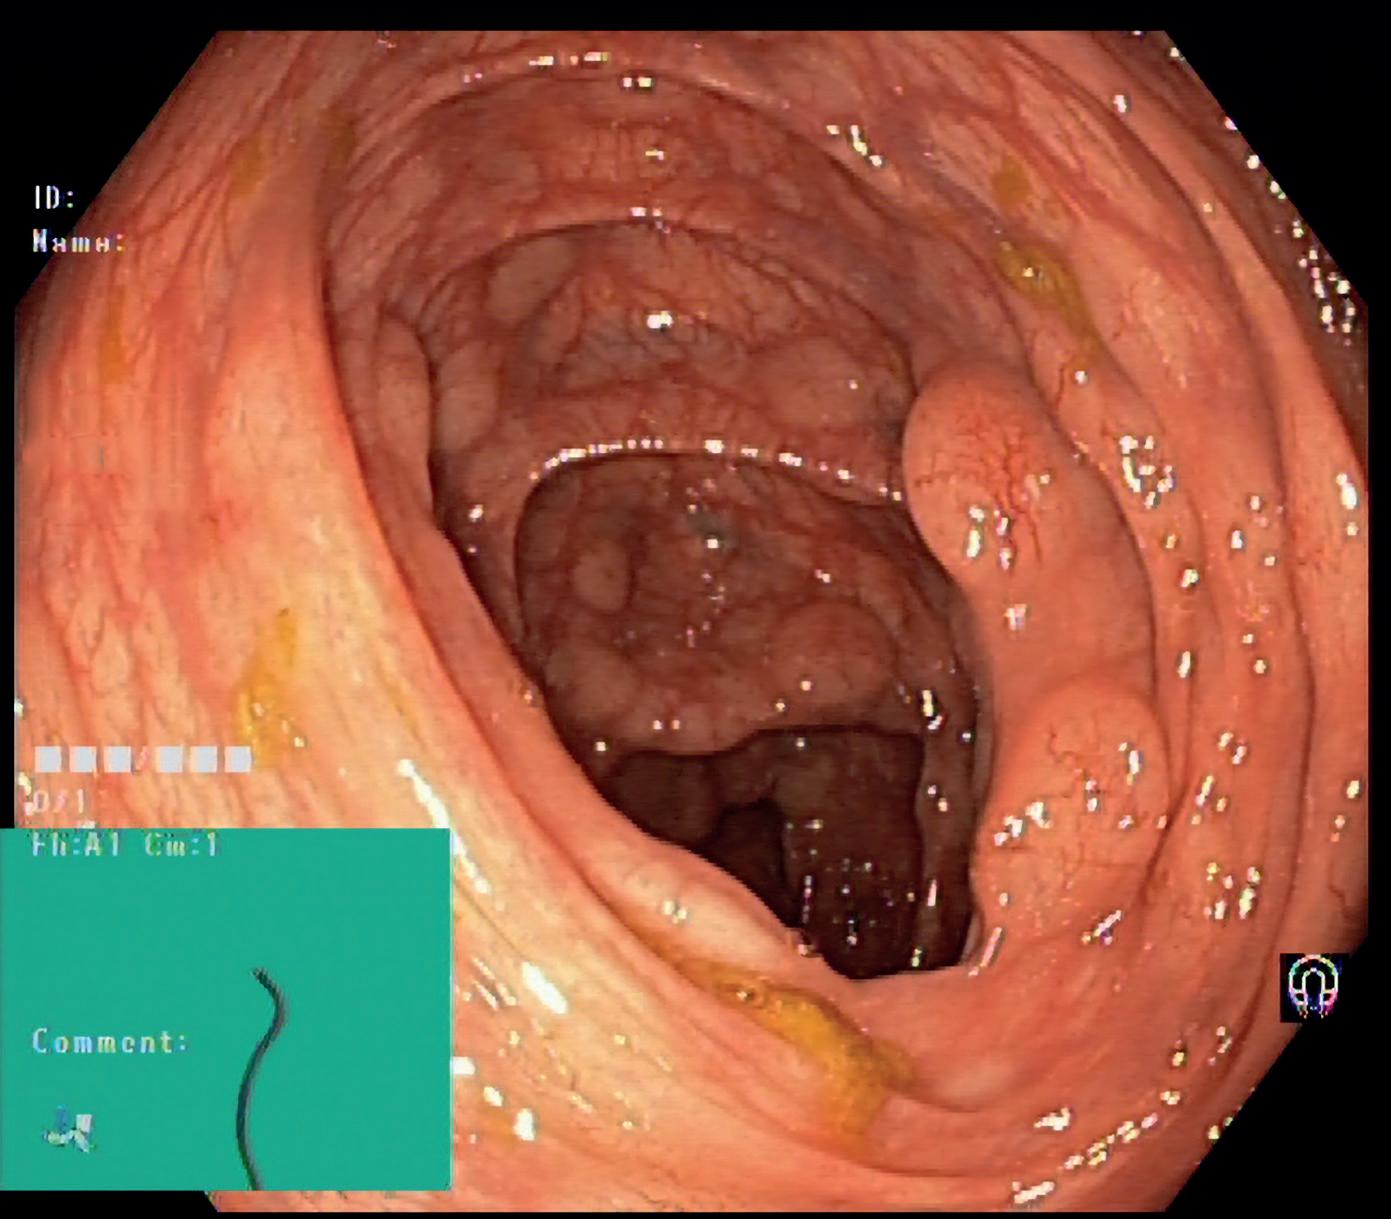

Hepatocellulært karsinom: Radiologisk diagnostikk og stadieinndeling

LI-RADS klassifikasjonen

Hos pasienter med høy risiko for HCC kan man i stor grad stille diagnose ved bildeundersøkelse alene. Det er derfor avgjørende å vite om pasienten tilhører en høyrisikopopulasjon med økt pre-test sannsynlighet for HCC. Høyrisikopopulasjonen begrenser seg til pasienter med etablert levercirrhose, aktuell eller tidligere gjennomgått HCC, eller non-cirrhotisk kronisk HBV-infeksjon med visse tilleggsfaktorer.

LI-RADS (Figur 1), publisert av American College of Radio logy, er en god veileder og mal for radiologisk utredning av pasienter som tilhører høyrisikopopulasjonen (1). Det viktigste diagnostiske kriteriet for radiologisk påvisning av HCC er kontrastoppladningsmønsteret, både på CT, MR og ultralyd med kontrast. HCC har hovedsakelig arteriell kontrastoppladning og viser typisk et tidlig, kraftig og ujevnt oppladningsmønster, særlig i litt sen arteriefase. Deretter sees typisk utvasking av kontrast.

I LI-RADS angis at både den kraftige initiale kontrast oppladningen og utvaskingen taler sterkest for HCC hvis den er henholdsvis «nonrim» og «nonperipheral», altså sees i mer sentrale deler av tumor. Andre hovedtrekk som kan indikere HCC er kontrastforsterket kapsel og terskelvekst. Dertil finnes en rekke andre karakteristika, men ingen av disse er absolutt spesifikke for HCC. Ved LI-RADS 5 og LI-RADS 4 er sannsynligheten for at det foreligger HCC henholdsvis 95% og 74%.

Figur 1. LI-RADS klassifikasjonen for radiologisk diagnostikk av hepatocellulært karsinom. Ved LR-5 og LR-4 er sannsynligheten for at det foreligger hepatocellulært karsinom henholdsvis 95% og 74%.